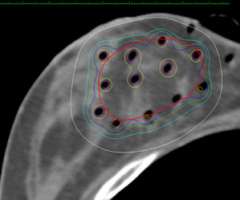

Below is an example of a case here at UCLA where we were able to spare the majority of the implant from receiving unnecessary radiation while achieving optimal coverage around the lumpectomy cavity.

Example of a partial breast case done at UCLA in a woman with breast augmentation who had a SAVI applicator placed. One can see that the distribution of the radiation dose as can be seen in the colored lines is focused around the lumpectomy cavity and that the majority of the implant (light grey) is spared from unnecessary radiation. A different view of the same patient with the SAVI applicator in the lumpectomy cavity just above the implant outlines in yellow.